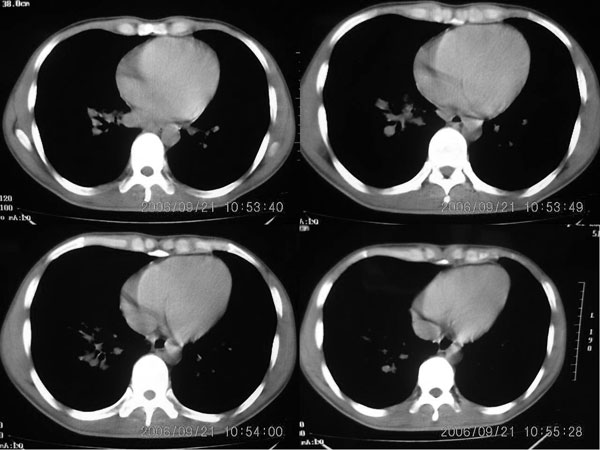

右肺门阴影增大,见有钙化,右肺下叶后基底段片状影,结合治疗史考虑右肺下叶结核

右下肺后基底段病灶虽然具有周围型肺癌的一些征象,但是它太虚了,纵肺比例过小,不到50%。而且在纵隔窗也显示该病灶比较虚,“块儿”比较小,内部也不实在,有小泡。

单就此病灶来说,考虑结核更为妥当。但问题是右肺门以及纵隔多组淋巴结肿大不太好解释,再有就是双肺的粟粒病灶,如果是血播的话应该有很明显的症状、体征的,不至于象楼主这般轻描淡写。

肺部有这么多病灶,临床症状却不多,我认为首先应该考虑:细支气管肺泡癌。

m 27 右肺门影增大,纵隔内可见多个淋巴结肿大,右肺下叶内后基底段斑片状模糊影,两肺间质性改变;考虑结节病或结核,建议纤维支气管镜穿刺活检.鉴别诊断1;淋巴瘤,纵隔淋巴肿大(胸骨后淋巴肿大突出)进展快,范围不够大,无融合及包埋改变..2结核其淋巴结密度是不均匀的,其内部一般有干酪坏死.可有钙化.可做ppd试验进一步明确.3结节病往往表现为肺门淋巴结对称性肿大.